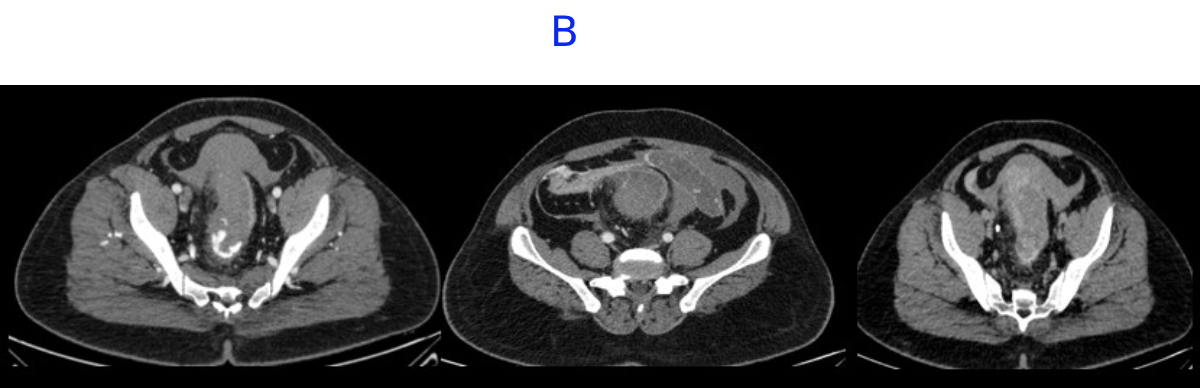

B. LEGENDS

- Distal rectum and proximal sigmoid colon mild edematous wall thickening.

- Hemorrhagic fluid noted in bilateral paracolic gutter and pelvis with active contrast extravasation.

- Omentomesenteric fat stranding in lower abdomen with mesorectal fascial thickening noted.